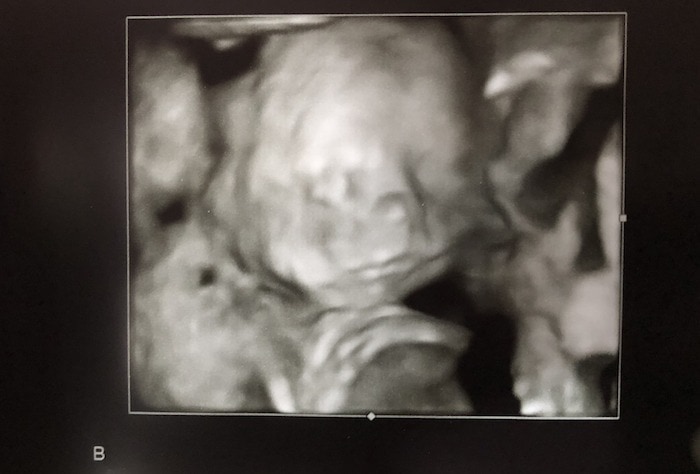

Ultrasound Photos at 21 Weeks Pregnant With Twins